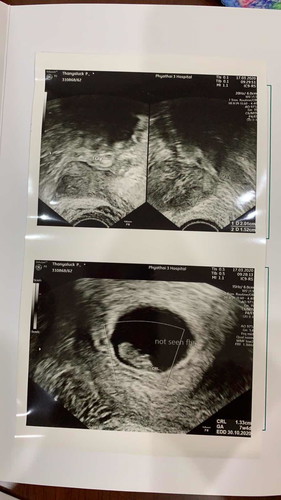

ตั้งท้องได้8สัปดาห์ มีเลือดออกปวดท้อง ไปหาคุณหมอ คุณหมอบอกว่าไม่เห็นหัวใจและไม่ได้ยินเสียงหัวใจน้องเลยค่ะ คุณหมอเอาน้องออกพร้อมขูดมดลูกเพราะเสียเลือดมาก สูญเสียน้องไปแล้วค่ะ ไม่อยากจะเชื่อ

มีเลือดออก คุณหมอซาวด์ดูพบว่าน้องไม่มีหัวใจน้องได้8สัปดาห์ค่ะ น้องเสียแล้วค่ะ